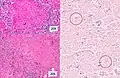

One proposed mechanism is that tuberculous infection in the lungs results in erosion of the epithelial layer of alveolar cells and the spread of infection into a pulmonary vein.[12][13] Once the bacteria reach the left side of the heart and enter the systemic circulation, they may multiply and infect extrapulmonary organs.[13] Once infected, the cell-mediated immune response is activated. The infected sites become surrounded by macrophages, which form granuloma, giving the typical appearance of miliary tuberculosis.[14]

A case of miliary tuberculosis in an 82-year-old woman: